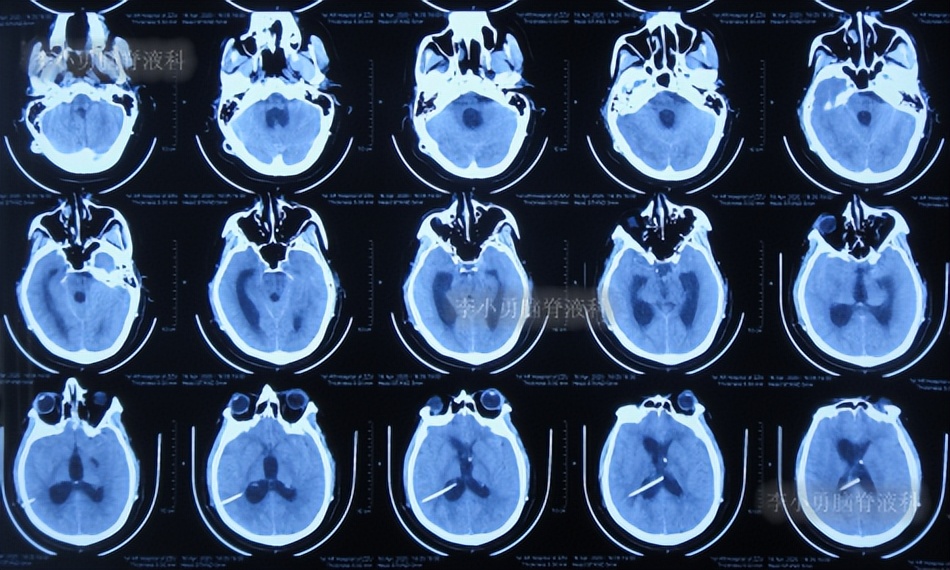

于是次日即2019年10月4日,第3次就诊于给予手术的省级三甲医院,入院次日查头颅核磁(图-2)后考虑引流管堵塞,给予了脑室分流管探查调整术。

图-2:2019年10月5日头颅核磁

脑室分流管探查调整术后5天即2019年10月10日,患者症状好转,查头颅CT示脑室缩小(图-3)。

图-3:2019年10月10日头颅CT

第3次出院后24天即2019年11月10日,因视物又出现模糊,在当地医院查头颅CT示脑室又有扩张(图-4),给予手术的医生建议继续观察。

图-4:2019年11月10日头颅CT

第3次出院后72天即2019年12月28日,再次出现头晕伴有恶心,在当地的医院查头颅核磁(图-5)后微信传给给予手术的医生,医生建议到院治疗。

图-5:2019年12月28日头颅核磁

于2019年12月30日(鞍上池脑囊虫切除术+三脑室造瘘术后近2年,第3次出院后74天即脑室腹腔分流术后1年零9个月;又即脑室分流管探查调整术近3个月),第4次就诊于给予手术的医院,考虑脑积水加重。

入院次日2019年12月31日,进行了第2次的左侧脑室腹腔分流术(图-6)。

图-6:2019年12月31日头颅CT